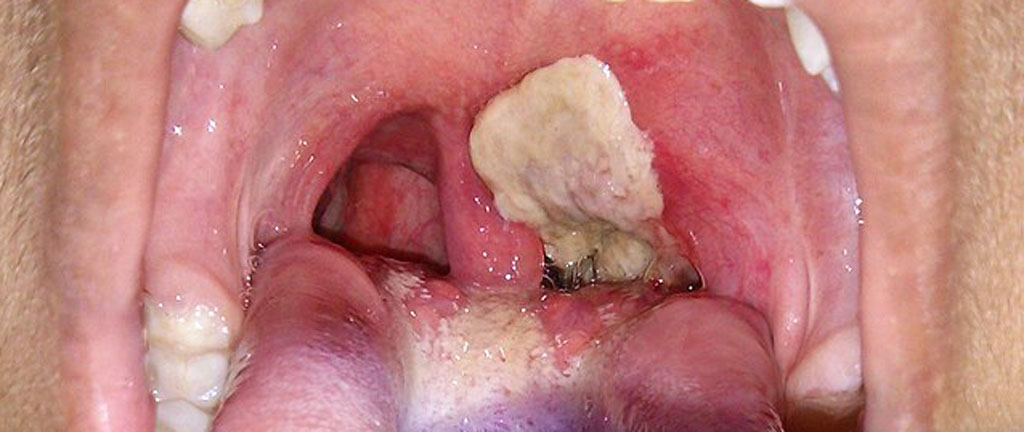

Svalgdifteri börjar med halsont, heshet och feber. Sjukdomen kan snabbt förvärras med andningssvårigheter, förstorade halslymfkörtlar och tjocka, gråa beläggningar i svalget som kan blockera luftvägarna (”äkta krupp”). Toxinet kan orsaka hjärtmuskelinflammation, njurskador och nervförlamningar.